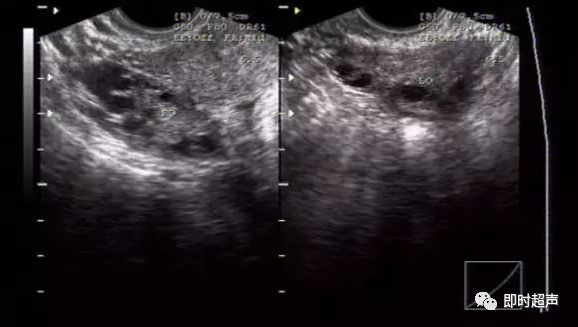

双侧卵巢的显示,与腹式超声比较,内部结构明显清晰。图片上可见数个未成熟卵泡。